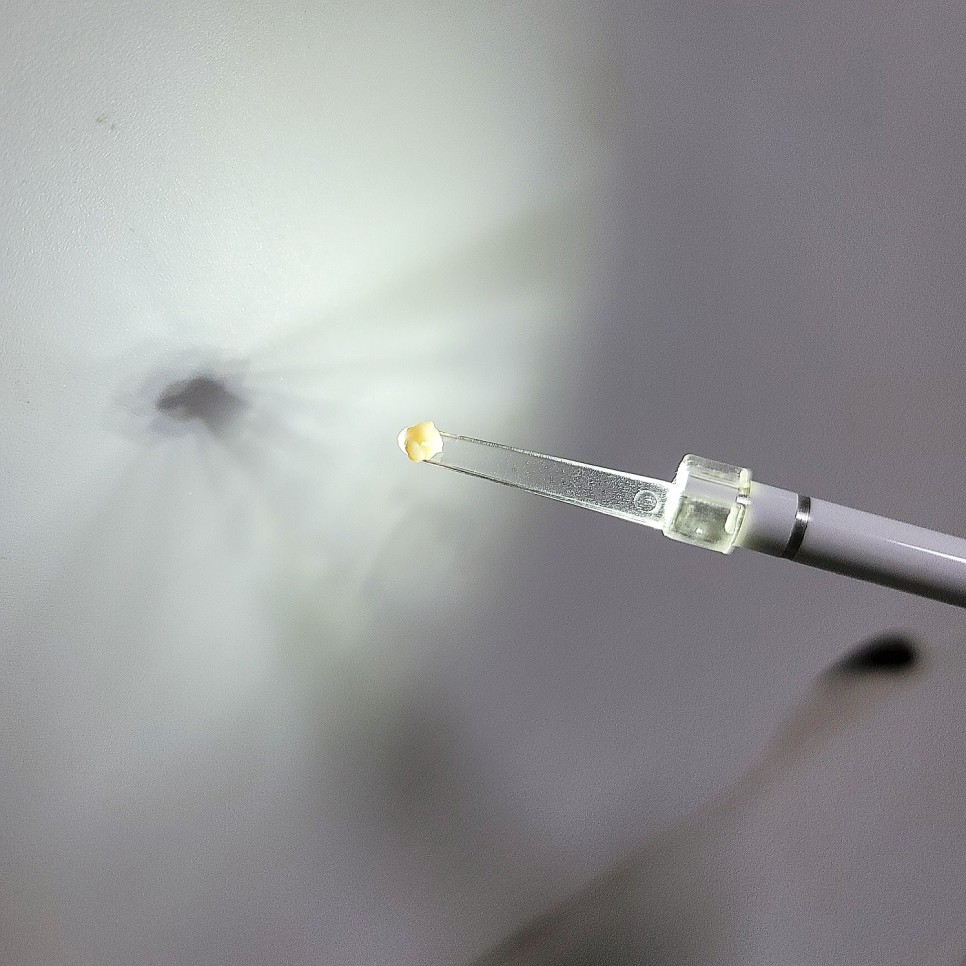

WoW…… 역시 예상대로 편도결석이 맞아서 의사고객님께서 흡입기(?)로 제거해주셨다.구역질이 나서 죽을뻔했다………눈물 또 흘립니다………지금보니 가끔 입안에서 저런 돌멩이?가 나오니까..내가 양치질을 안해서, 지금까지 먹은것중 하나인줄 알았는데..ㅋㅋㅋㅋㅋㅋㅋㅋㅋㅋㅋㅋㅋㅋㅋㅋㅋㅋㅋㅋㅋㅋㅋㅋㅋㅋㅋㅋㅋㅋㅋㅋ지금보니 그동안 편도결석이 저절로 떨어진것 같다.탱글탱글 이번에는 목의 붓기가 동시에 일어나 민감하게 받아들인 결과로 빨리 발견한 것 같습니다.